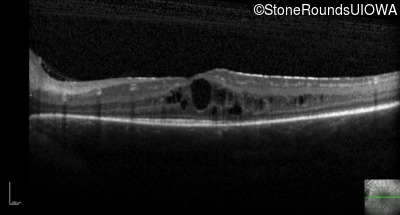

Optical Coherence Tomography - Right - 20/30 -2

Exemplar / OCT Stack